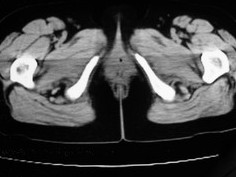

女42岁肛门下坠感4月余.

子宫轻度右倾,体后方见小似新月形低密度区,边界清楚。余所见无明显异常。

子宫轻度右倾,体后方见小似新月形低密度区,道格拉斯窝周围间隙欠清晰,有索条模糊影阴,多考虑:肛周脓肿可能性大。

肛周脓肿临床症状比较典型,此患者:女42岁肛门下坠感4月余,与其不符

子宫轻度右倾,体后方见小似新月形低密度区,道格拉斯窝周围间隙欠清晰,有索条模糊影阴,多考虑:肛周慢性感染可能。